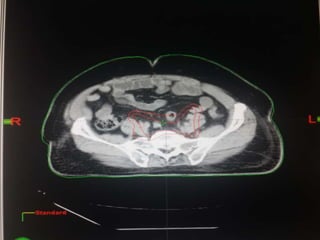

RTOG GU Consensus on pelvic LN CTV volumes:

 Commence contouring the pelvic CTV LN volumes at the L5/ S1

interspace (the level of the distal common iliac and proximal

presacral lymph nodes).

 Place a 7-mm margin around the iliac vessels connecting the

external and internal iliac contours on each slice, carving out

bowel, bladder, and bone.

 Contour presacral lymph nodes from S1 through S3, posterior

border being the anterior sacrum, and anterior border

approximately 10 mm anterior to the anterior sacral bone

carving out bowel, bladder, and bone.

 Stop external iliac CTV lymph node contours at the top of the

femoral heads (bony landmark for the inguinal ligament).

 Stop contours of the obturator CTV lymph nodes at the top of

the symphysis pubis.

RTOG GU Consensuson pelvic LN CTV volumes:  Commence contouring the pelvic CTV LN volumes at the L5/ S1 interspace (the level of the distal common iliac and proximal presacral lymph nodes).  Place a 7-mm margin around the iliac vessels connecting the external and internal iliac contours on each slice, carving out bowel, bladder, and bone.  Contour presacral lymph nodes from S1 through S3, posterior border being the anterior sacrum, and anterior border approximately 10 mm anterior to the anterior sacral bone carving out bowel, bladder, and bone.  Stop external iliac CTV lymph node contours at the top of the femoral heads (bony landmark for the inguinal ligament).  Stop contours of the obturator CTV lymph nodes at the top of the symphysis pubis.